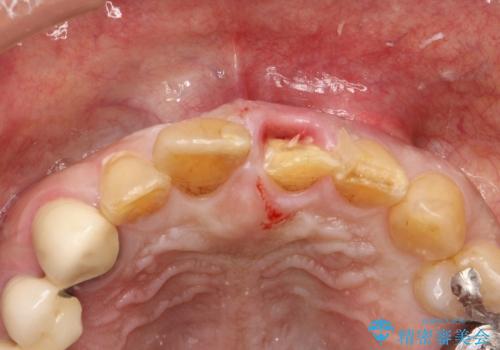

左上1が水平的に割れている状態で、歯冠を取り除くと神経が露出しており、唇側はかなり歯肉縁下で破折しており、そのままではかぶせものを入れるのは難しい状態でした。

根管治療をした上で歯を引っ張りだして(エクストリュージョン)、その後、骨外科にて歯周組織を整えた上で、かぶせものを入れていく治療計画をたてました。

歯を引っ張りあげたり、手術をしたあとの治り待ちをしたり、治療に時間がかかる方法ではありましたが、抜かずにその歯を使うことができたことで、患者さんにはとても満足していただけています。